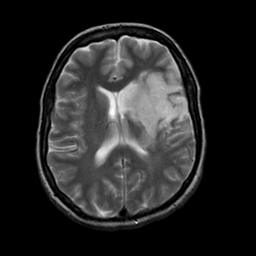

Acute Stroke: T2-weighted MR -- Slice #15

Tour 1: Next/Previous/Start: Note how the conventional T2-weighted images have converted to high signal in the lesion at four days after onset of symptoms. Compare these images with the diffusion-weighted MR images obtained acutely (below)